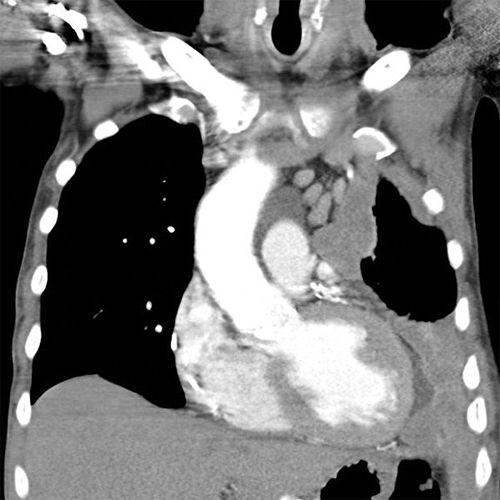

Coronal reformat of a CT of the chest in a patient with right sided medial mesothelioma. Note the extensive pleural mass with contraction of the right hemithorax. Source: Frank Gaillard, Radiopaedia